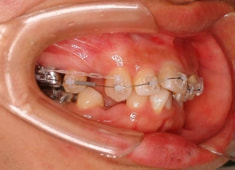

治療開始時